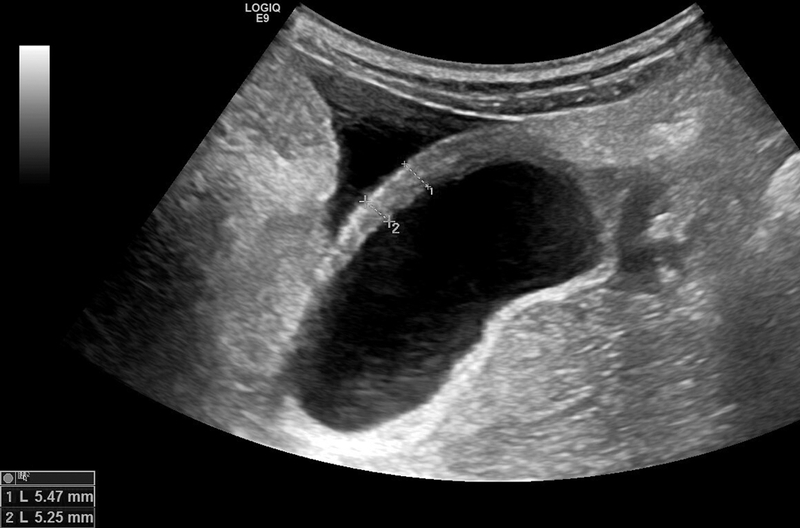

Dày thành túi mật là đặc điểm đặc trưng của viêm túi mật cấp và bệnh lý túi mật nguyên phát. Tuy nhiên, dấu hiệu này không phải là đặc hiệu, có thể xuất hiện đồng thời trong nhiều bệnh lý túi mật khác, ngoài túi mật. Thành túi mật được coi là dày khi có độ dày hơn 3mm và thường hiển thị dưới dạng xếp lớp trên kết quả siêu âm. Trên kết quả chụp CT, thành túi mật thường có một lớp phù dưới thanh mạc, có thể bị nhầm lẫn với dịch quanh túi mật (pericholecystic fluid).

Thành túi mật bình thường, thường xuất hiện như một đường tăng âm mảnh trên phim chụp siêu âm. Độ dày của thành túi mật có thể thay đổi tùy thuộc vào mức độ căng của túi mật và hiện tượng giả dày thành túi mật cũng có thể xảy ra sau khi ăn.

Viêm túi mật cấp tính thường là nguyên nhân chính dẫn đến dày thành túi mật trong các kết quả chẩn đoán hình ảnh. Ngoài viêm túi mật cấp, một số biểu hiện khác có thể gặp là: Sỏi mật gây tắc nghẽn, túi mật căng to và ứ dịch, đau ở vị trí túi mật khi ấn bằng đầu dò siêu âm, viêm thâm nhiễm mỡ hoặc dịch tụ xung quanh túi mật, cũng như tăng tưới máu thành túi mật (hiển thị trên kết quả siêu âm Doppler).